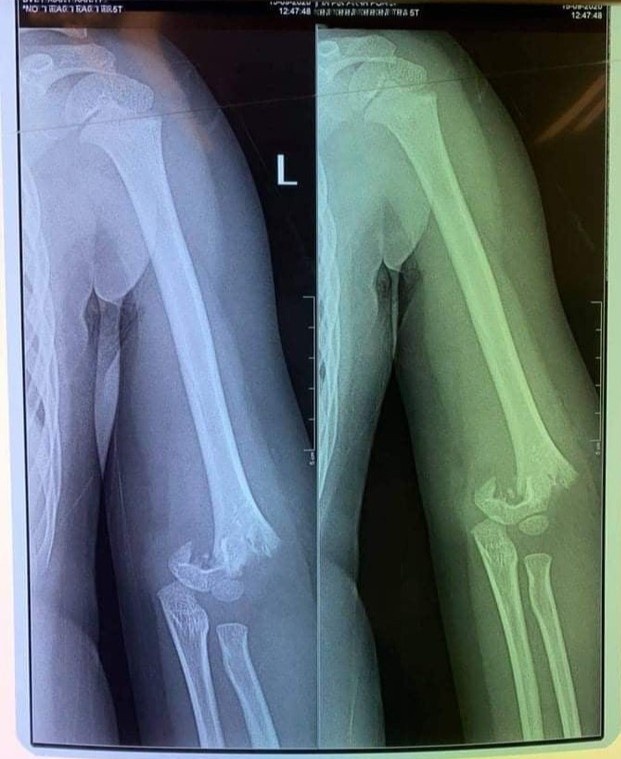

Hình ảnh chụp phim cho thấy trẻ bị gãy xương cánh tay. Ảnh: Gia đình cung cấp.

Trước đó, một phụ huynh có con đi học ở trường Mầm non Vườn Trẻ Thơ thông tin trong giờ học ngoài trời, con bị bạn xô ngã dẫn đến gãy tay. Khi nhà trường đưa con đến viện chụp chiếu, tay con bị gãy phải mổ. Sự việc xảy ra cách đây khoảng chục ngày nhưng gia đình bận chăm sóc con đến nay mới thông tin sự việc.